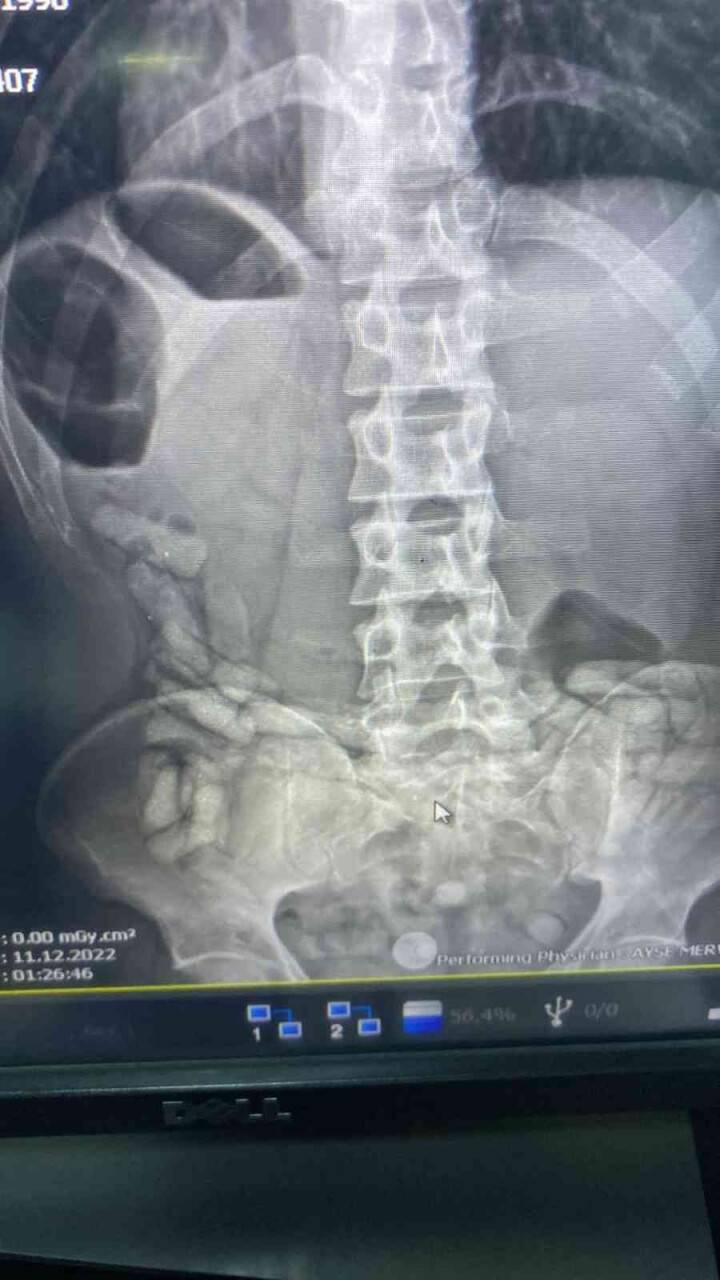

Ağrı Narkotik Suçlarla Mücadele Şube Müdürlüğü'nce uyuşturucu madde ticareti, kullanımı ve sokak satıcılarının faaliyetlerini önlemeye yönelik yapılan çalışmalar neticesinde yakalanan İran uyruklu A.G. isimli kişinin Doğubayazıt Devlet Hastanesi'nde yapılan iç beden muayenesinde, midesinde yabancı maddeler olduğu tespit edildi. A.G.'nin midesinden çıkarılan 55 kapsül halinde toplam 432 gram afyon sakızına el konuldu. Şahıs, "uyuşturucu veya uyarıcı madde ticareti yapma veya sağlama" suçundan sevk edildiği adli makamlarca tutuklandı.